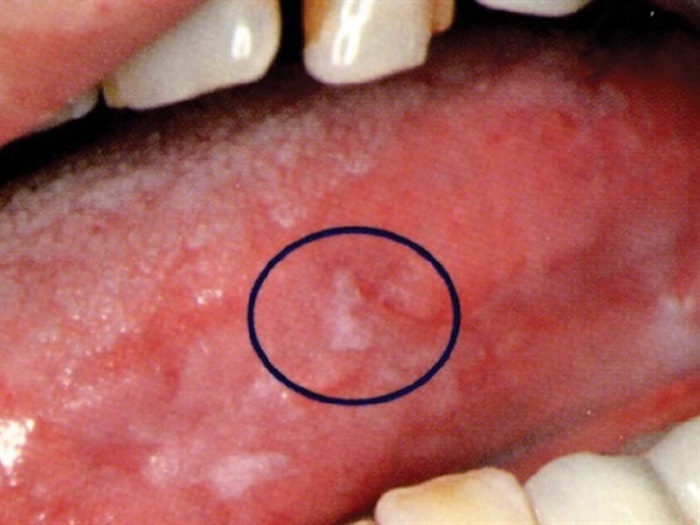

Os principais sintomas de câncer na língua são: Dor na língua que não passa; Manchas vermelhas ou brancas na língua e na cavidade oral, que podem também ser doloridas; Desconforto para engolir e para mastigar; Mau hálito; Sangramento na língua, que pode ser notado principalmente quando se morde ou mastiga, por exemplo; Dormência na boca;

Quais são seus sintomas? Dentre os principais sintomas dessa doença, estão: feridas e aftas na língua que não cicatrizam; dor na língua; dificuldade para falar ou engolir; manchas avermelhadas ou esbranquiçadas; caroços na língua; sangramento ao morder ou mastigar.

O câncer na língua ou câncer de boca, aparece normalmente devido a uma ferida na língua que teima em não cicatrizar ficando sempre aberta e dolorida. Este tipo de enfermidade nasce e se desenvolve nas células que ficam nas partes mais salientes da língua. Pode causar graves lesões e até mesmo derivar para tumores.